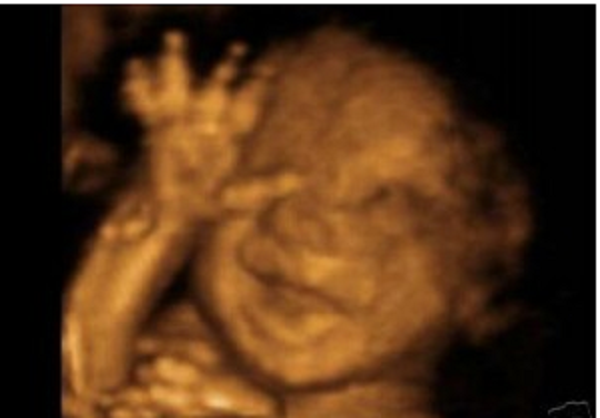

Today a Minnesota Senate committee passed, along party lines, a bill for an amendment to enshrine unlimited abortion in the state Constitution. The bill, SF 473, would put a proposed constitutional amendment on the ballot for voters in the fall; the amendment is a version of the so-called Equal Rights Amendment (ERA) that, among other controversial provisions, would establish in the Constitution a right to abortion without limits at any stage of pregnancy.